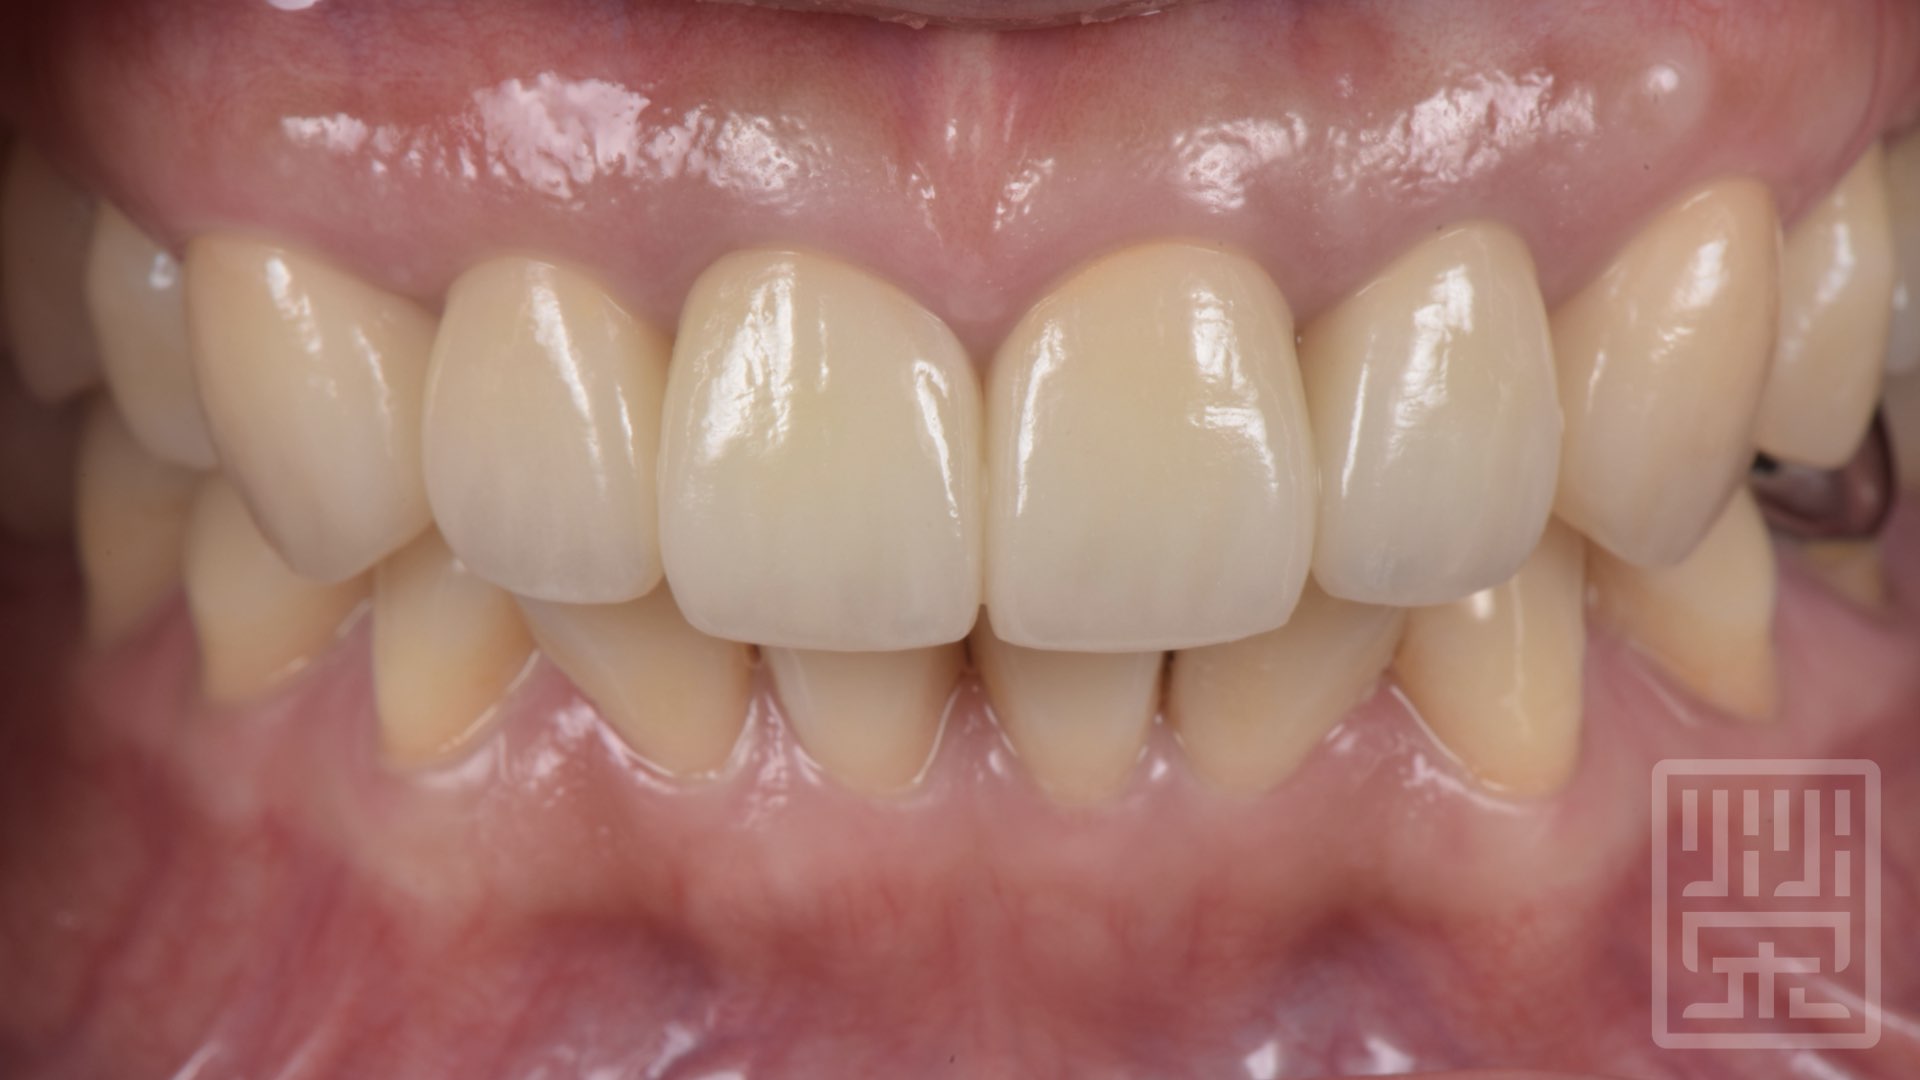

榮醫師建議他兩側上顎犬齒也一起更換全瓷冠,保護牙齒,重新建立保護性咬合。

植牙全瓷冠修復

保護性咬合

自信開心的微笑